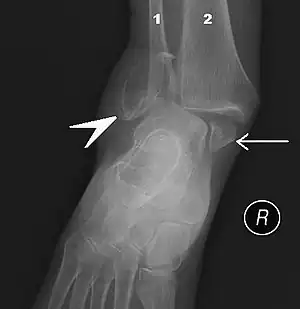

Fracture of both sides of the ankle with dislocation as seen on anteroposterior X-ray. (1) fibula, (2) tibia, (arrow) medial malleolus, (arrowhead) lateral malleolus

An ankle fracture is a break of one or more of the bones that make up the ankle joint.[20] Symptoms may include pain, swelling, bruising, and an inability to walk on the injured leg.[20] Complications may include an associated high ankle sprain, compartment syndrome, stiffness, malunion, and post-traumatic arthritis.[20][21]

Ankle fractures may result from excessive stress on the joint such as from rolling an ankle or from blunt trauma.[20][21] Types of ankle fractures include lateral malleolus, medial malleolus, posterior malleolus, bimalleolar, and trimalleolar fractures.[20] The Ottawa ankle rule can help determine the need for X-rays.[21] Special X-ray views called stress views help determine whether an ankle fracture is unstable.